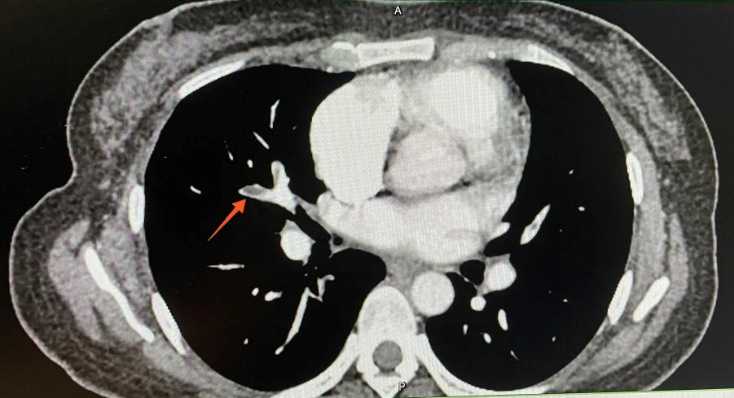

患者女,37岁,因“左下肢肿胀1天”于2021年07月10日入中山大学第一附属医院。中山大学第一附属医院下肢血管彩超提示双下肢静脉提示深静脉血栓形成,肺动脉CT可见双肺多发血栓形成(图1)。患者经抗凝溶栓治疗1个月后,于2021年08月04日出现大量阴道流血,并于2天后于家中昏迷,遂于2021年8月6日入暨南大学第一附属医院,诊断为子宫肌瘤。患者近期无外伤史、无输血史、无血液系统疾病史,无吸烟、吸毒史,近期无口服短效避孕药史,未婚未育,2年来有月经增多、经期延长、痛经史(月经周期28天,经期9~10天),体重正常,BMI 21.6 kg/m2。查体:生命体征平稳,贫血貌,宫底平脐上二横指,表面光滑,质硬,边界清,活动性差;双附件未触及。左下肢均匀凹陷性水肿,伴轻微疼痛,左下肢周径分别为左小腿39.5 cm (右侧37 cm),膝盖47 cm (右侧42.5 cm),大腿59 cm (右侧55.5 cm)。双下肢彩超提示:左侧大隐静脉根部及左侧股总、股浅、腘静脉血栓形成(图2)。B超提示:子宫体积增大,切面内径175 mm × 118 mm × 140 mm,实质回声欠均匀。内膜显示不清。宫腔内见一不均质低回声团,大小约117 mm × 146 mm × 117 mm,边界尚清。宫底肌层见一个实性低回声团,大小约44 mm × 56 mm × 48 mm,形状呈椭圆形,内部为低回声,分布均质,边缘清楚。盆腔MR提示:子宫后壁肌层见巨大类圆形异常信号影,大小约14.9 cm × 9.8 cm × 14.2 cm,病灶与子宫后壁肌层分界不清,增强扫描呈明显不均匀强化,考虑子宫平滑肌瘤与子宫平滑肌肉瘤相鉴别(图3)。血浆D-二聚体定量4270 ng/ml,血红蛋白HGB 61.30 g/L,蛋白S17.7%,抗磷脂抗体未见明显异常。入院后予缩宫素促进子宫收缩、促性腺激素释放激素激动剂(Gn-RHa)止血、生血宁纠正贫血、补液、输血、抗凝等对症处理后转介入科治疗血栓。于2021年8月16日行左下肢静脉造影 + 下腔静脉滤器植入术(图4)。DSA显示:左下肢股静脉、股总静脉上段、髂静脉、下腔静脉未见显影,股、髂静脉周围可见大量侧枝循环形成。术后予利伐沙班10 mg qd口服、升血宝15 ml tid + 红源达1片bid口服。患者病情稳定后复查CT示双肺肺动脉内多发血栓基本吸收,超声示肌瘤体积减小。遂于2021年8月30日在腰麻下行腹式子宫肌瘤剔除术,术中见子宫均匀增大如孕4月大小,质硬,表面光滑,宫底部见一带蒂浆膜下肌瘤,大小约60 mm × 50 mm × 50 mm。子宫及卵巢表面见炎性粘连带。术中病理冰冻结果:子宫平滑肌瘤伴玻璃样变性。手术顺利,两个肌瘤(总重量约900 g)在手术中被完全切除,未穿透子宫腔,术中出血约500 ml,患者未诉特殊不适。术后常规预防感染,低分子肝素抗凝治疗,复查患者血浆d-二聚体浓度降至670 ng/ml。术后4天取出下腔静脉滤器,患者活动后无不适出院,予利伐沙班口服半年预防血栓复发,并予Gn-RHa连续治疗3个周期,定期随访有无新发血栓形成。

Figure 3. Pelvic MR: A large circular abnormal signal shadow is seen in the muscle layer of the posterior wall of the uterus, which compresses the iliac vein

3. 盆腔MR:子宫后壁肌层见巨大类圆形异常信号影,压迫髂静脉